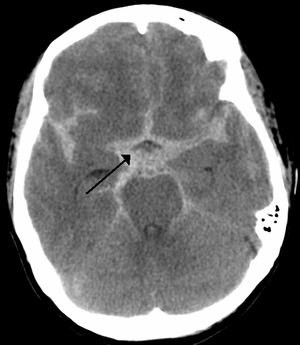

| CT scan of the brain showing subarachnoid hemorrhage as a white area in the center and stretching into the sulci to either side (marked by the arrow) | |